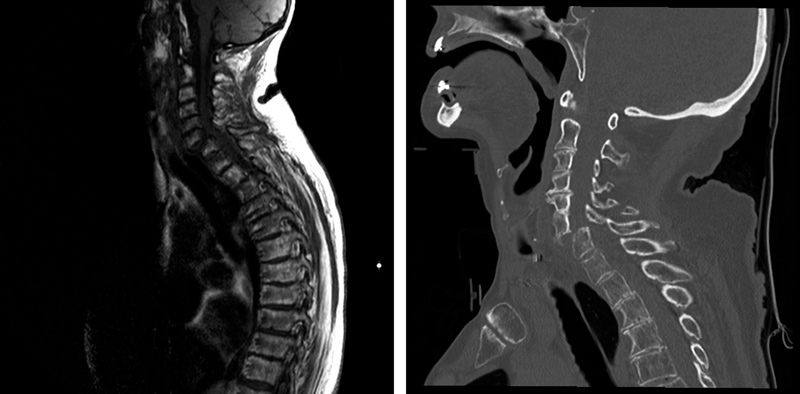

ECG showed rapid atrial fibrillation. She was examined with CT of the head, blood tests, urine dipsticks, arterial blood gas, rhythm monitoring and EEG on suspicion of infection, arrhythmia or epileptic seizures. CT of the head showed recurrence of a previously operated right frontal meningioma and a new left parietal meningioma. EEG two days after admission showed no epileptiform activity. The neurologist who saw the spasms during EEG recording considered dystonia. However, the frequent right-sided movements had the same flexion pattern as the inverted plantar reflex, consistent with the Babinski sign (video). The spasms continued to occur spontaneously, sometimes also on the left side, and could be triggered by light touch. The neurologist therefore suspected myelopathy. A new neurological examination found the patient to have bilaterally reduced hand grip strength, and lower limb spasticity. Acute MRI showed cervical myelopathy (image on left), and a CT of the neck revealed a dislocation fracture at level C6/C7 with compression of the spinal cord (image on right). Upon transfer to the neurosurgical department she was tetraparetic but with preserved sensibility. She underwent immediate posterior fixation and, after two days, reoperation with anterior fixation at level C6/C7. The spasms in her feet disappeared, but she had persistent distal paralysis in her legs and arms and grade 2 – 4/5 proximal paresis. The woman died shortly afterwards.